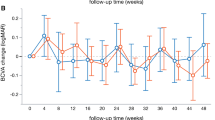

Mean BCVA at baseline was 0.37 ± 0.26 logMAR in the ETRP group and 0.40 ± 0.27 logMAR in the CPRP group (P = 0.44). The mean BCVA 3 months post-laser was 0.47 ± 0.19 and 0.47 ± 0.24 logMAR in the ETRP and CPRP groups, respectively. Though VA decreased significantly in both groups, the difference was not significant between the groups (P = 0.68, Table 2). At 3 months, 85 (64.4%) and 82 (60.7%) eyes had stable or improved BCVA while 50 (35.6%) and 53 (39.3%) eyes had worsened VA in ETRP and CPRP groups, respectively (P = 0.54).

As shown in Table 1, the difference of baseline CMT was insignificant between the groups: 245 ± 26 vs. 248 ± 28 µm in the ETRP and CPRP groups, respectively (P = 0.36). Three months following laser, mean CMT increased to 285 ± 40 and 281 ± 44 µm in the ETRP and CPRP groups, respectively (Table 2). Although these changes were significant in both arms (41.08 µm in the ETRP group, 95% CI 33.52–48.64, P < 0.001 and 33.31 µm in the CPRP group, 95% CI 24.90–41.72, P < 0.001), the difference between the groups was not significant (P = 0.26). Furthermore, the changes of VA (logMAR) and CMT were found to be correlated positively among patients (r = 0.165, P = 008). However, eyes with worsened BCVA had greater increase in CMT (mean increase difference 23 µm, 95% CI 12–36, P < 0.001) compared to the eyes with stable or improved BCVA.

In our study, 50 (35.5%) and 53 (39%) eyes lost ≥2 lines of vision in the ETRP and CPRP groups, respectively. This was comparable to other published reports, showing a range of 25–43% of eyes with VA worsening after laser [12–24]. In the diabetic retinopathy study, severe visual loss occurred in more than 10% of eyes after panretinal photocoagulation [4]. In Blankenship report, there was 8 and 24% of eyes with ≥2 lines VA worsening in the peripheral and central retinal photocoagulation groups, respectively [10]. However, Muqit et al. observed no change in VA at 4 and 12 weeks in 28 cases after pattern laser photocoagulation [11].

We found a positive linear correlation between VA and CMT changes. Therefore, CMT increase was the possible reason of BCVA worsening in our cases. McDonald and Schatz also reviewed 175 eyes and similar to our results reported that macular edema was the main cause of VA deterioration following PRP [25]. Other reasons for post-PRP diminishing VA in diabetic retinopathy include associated systemic diseases like hypertension, hyperlipidemia, nephropathy and also poor glycemic control [26–28]. The effects of these factors could be influential in longer period of times and therefore were not addressed in our study.